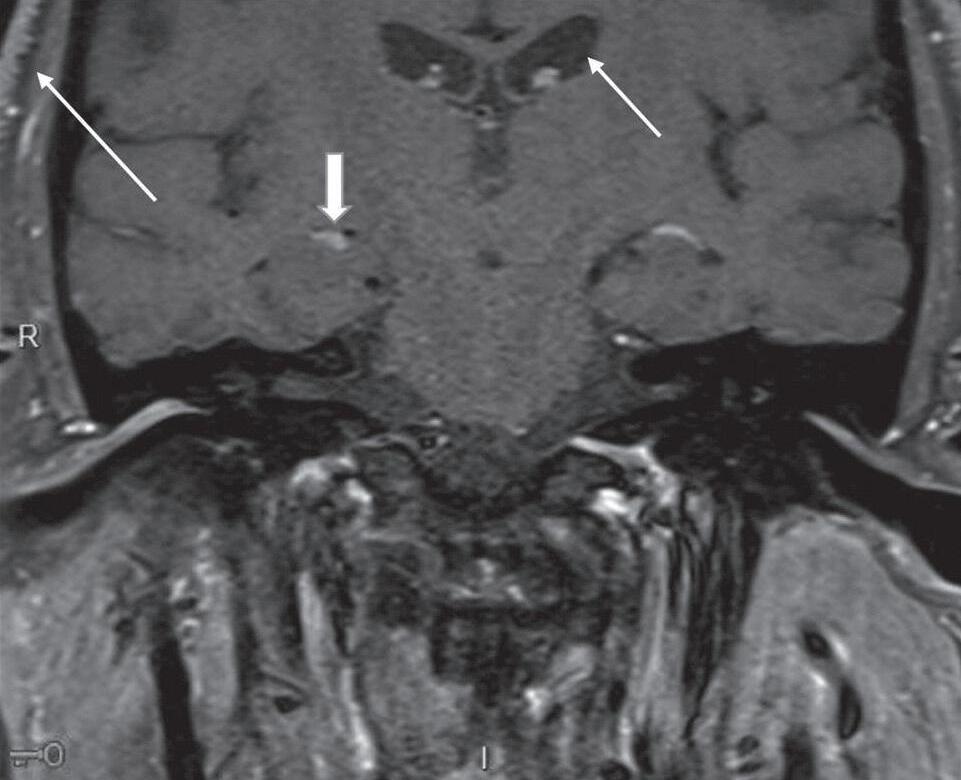

A angio TC e a angio RNM são importantes para o diagnóstico de aneurismas cerebrais, malformações arteriovenosas, estenoses e oclusões vasculares, trombose venosa cerebral, bem como conflitos neurovasculares. Além disso, podem ser utilizadas para o planejamento de procedimentos cirúrgicos, permitindo a visualização da anatomia dos vasos sanguíneos cerebrais antes da cirurgia. A angio RNM permite melhor acurácia e definição das estruturas vasculares intracranianas, sendo indicada em investigação de pequenos aneurismas e conflitos neurovasculares. A escolha entre os métodos abrange desde a suspeita clínica, urgência do diagnóstico e limitações relacionadas ao paciente, sendo a angio TC um método de menor custo e maior disponibilidade, enquanto a RNM é um exame com maior tempo para aquisição das imagens e contraindicações mais amplas, devendo-se avaliar previamente a compatibilidade de dispositivos gerais e materiais metálicos com o aparelho de RNM (Figs. 1-22 a 1-24).

Fig. 1-23. Paragangliomas jugulotimpânicos à esquerda e carotídeos bilaterais. RNM coronal T1 com supressão de gordura pós-Gd (a): lesão expansiva hipervascularizada no forame jugular esquerdo, com extensão à cavidade timpânica. Angio RNM sequência TRICKS pós-Gd (b): paraganglioma jugulotimpânico à esquerda (seta curta) e carotídeos (setas longas), individualizados na angio RNM, com enchimento precoce pelo agente paramagnético.